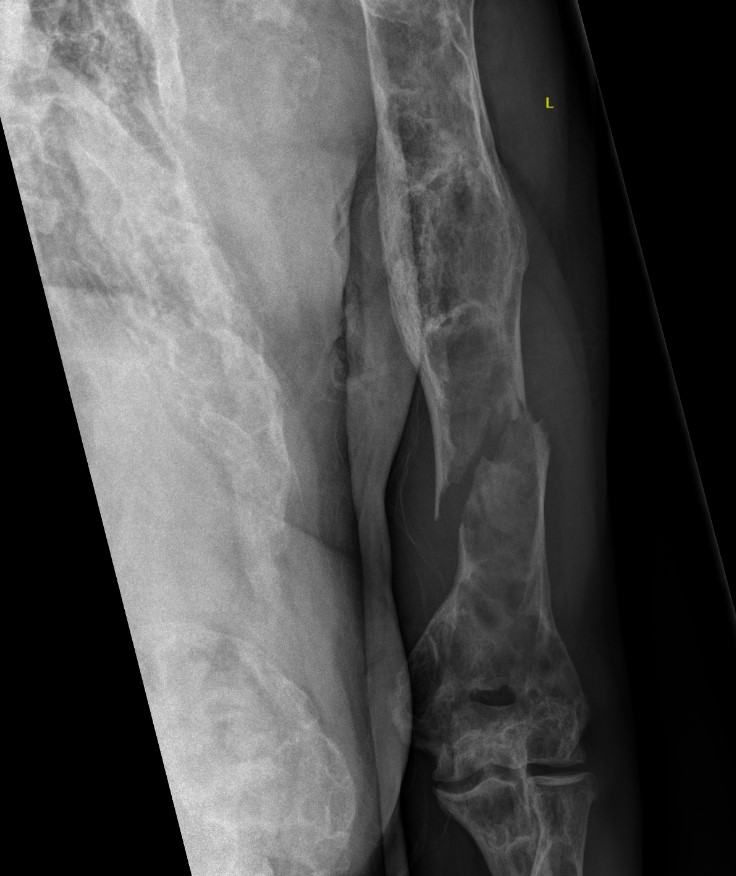

Coxa vara and Shepherd's Crook deformity of proximal femur

- Shepherd's Crook - anterior bowing of femur

- secondary leg length discrepancy

- pain, difficulty walking

Proximal femur coxa vara and shepherds crook deformity

- 11 cases

- initial osteotomy correction of coxa vara and fixation with hip plate

- later osteotomy and correction of shepherds crook / femoral bowing and insertion reconstruction nail

- improved pain and gait

- significant blood loss at both stages